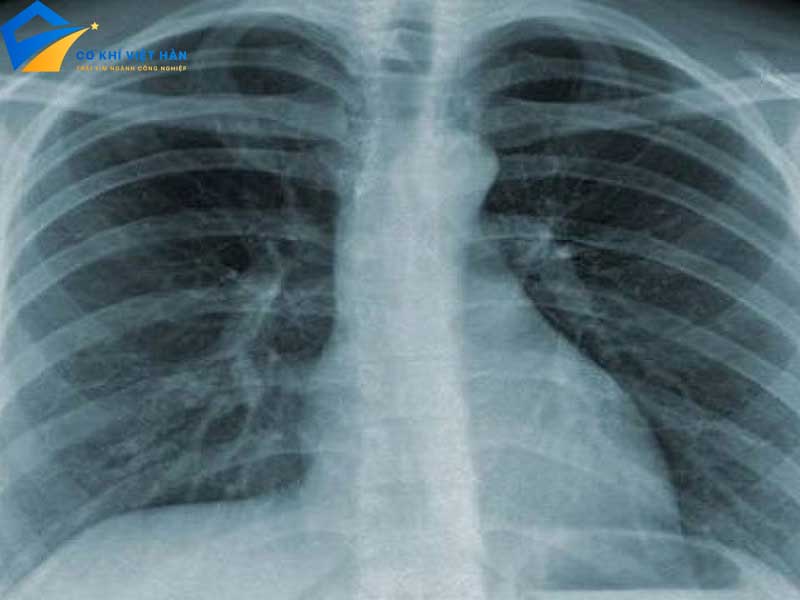

- Chụp X-quang: Là phương pháp chẩn đoán hình ảnh phổ biến nhất, giúp xác định tình trạng xương, mô và các cơ quan nội tạng.

Tính xuyên thấu: Tia X có khả năng xuyên qua các vật liệu khác nhau, từ xương cho đến mô mềm, điều này làm cho chúng trở thành công cụ quan trọng trong chẩn đoán hình ảnh.

Tác dụng lên phim ảnh: Khi tia X chiếu vào phim chụp, chúng tạo ra hình ảnh rõ nét, giúp bác sĩ xác định tình trạng sức khỏe của bệnh nhân.